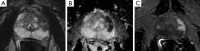

Figure 3

Multiparametric magnetic resonance imaging (mp-MRI) detects significant prostate cancer. This 63-year-old man had a doubling of serum PSA in less than 2 years. (A) A pseudonodular mass of the anterolateral part of the left mid-peripheral prostate with low signal on T2-weighted imaging (T2WI) is shown; (B) this mass is associated with low signal on the apparent diffusion coefficient (ADC) map signifying restricted diffusion; (C) focal asymmetric early enhancement on the arterial phase of the dynamic contrast-enhanced perfusion imaging. Targeted biopsies of this area revealed high volume Gleason 4+3=7 cancer. PSA, prostate-specific antigen.